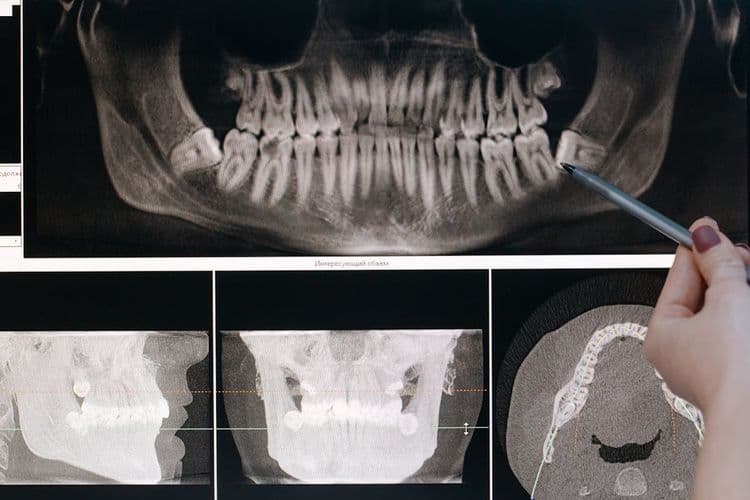

While the cost of wisdom tooth removal can vary considerably, one of the primary determinants is the complexity of the extraction procedure. Factors such as the tooth’s position, impaction level, and root morphology can necessitate advanced extraction techniques. Surgical extractions, requiring incisions and bone removal, often lead to higher costs compared to simpler, non-surgical removals. Additionally, impacted teeth, particularly those close to nerves or other critical structures, demand meticulous planning and execution, potentially increasing expenses. Recovery considerations also play a role; complex extractions may entail longer recovery periods, increasing post-operative care costs. Patients may require additional medications or follow-up appointments to manage complications, further influencing the overall financial outlay for the procedure. Ultimately, complexity is a critical cost variable.

How Complexity of Extraction Impacts Cost